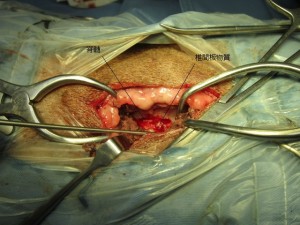

手術中の様子です。

椎弓を切除すると、大量の椎間板物質がでてきました。